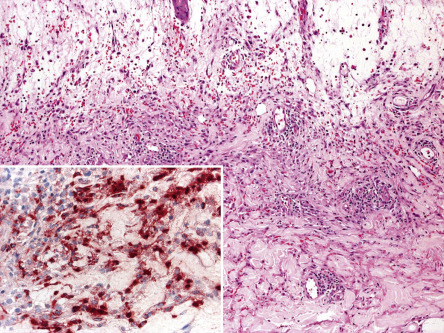

Three histologic variants of Sweet syndrome, histiocytoid, lymphocytic and eosinophilic, have been increasingly recognized. The histiocytoid variant is characterized by a dermal, and sometimes subcutaneous, infiltrate composed of histiocyte-like immature myeloid cells . These cells have myeloperoxidase activity ( Fig. 26.6 ) and must be distinguished from those of leukemia cutis. The lymphocytic variant is often associated with, and sometimes precedes, underlying myelodysplasia . More recently, an eosinophilic variant has been described .